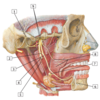

1 - facial artery and vein

2 - retromandibular vein

3 - external jugular vein

4 - anterior jugular vein

5 - common carotid artery

6 - internal jugular vein

7 - superior thyroid artery and vein

8 - external carotid artery

1 - vertebral artery

2 - costocervical trunk

#7 - common carotid artery

#1 - superficia temporal artery

#2 - occipital artery

#3 - internal carotid artery

#4 - external carotid artery

#5 - common carotid artery

#6 - superior thyroid artery & superior laryngeal branch

#7 - ascending pharyngeal artery

#8 - lingual artery

#9 - facial artery

#10 - posterior auricular artery

#11 - maxillary artery